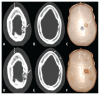

Ostéomyélite syphilitique chez un patient présentant des céphalées et des lésions lytiques